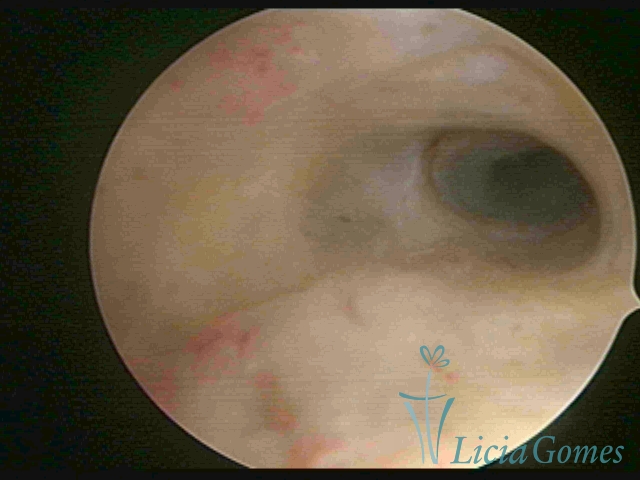

Primeira porção ou setor proximal ou setor inferior:

Durante a fase proliferativa, encontramos muco claro e cristalino pouco aderente à óptica. As criptas e as papilas apresentam-se um pouco edemaciadas e vascularizadas, micro vesicular, lembrando cachos de uva.